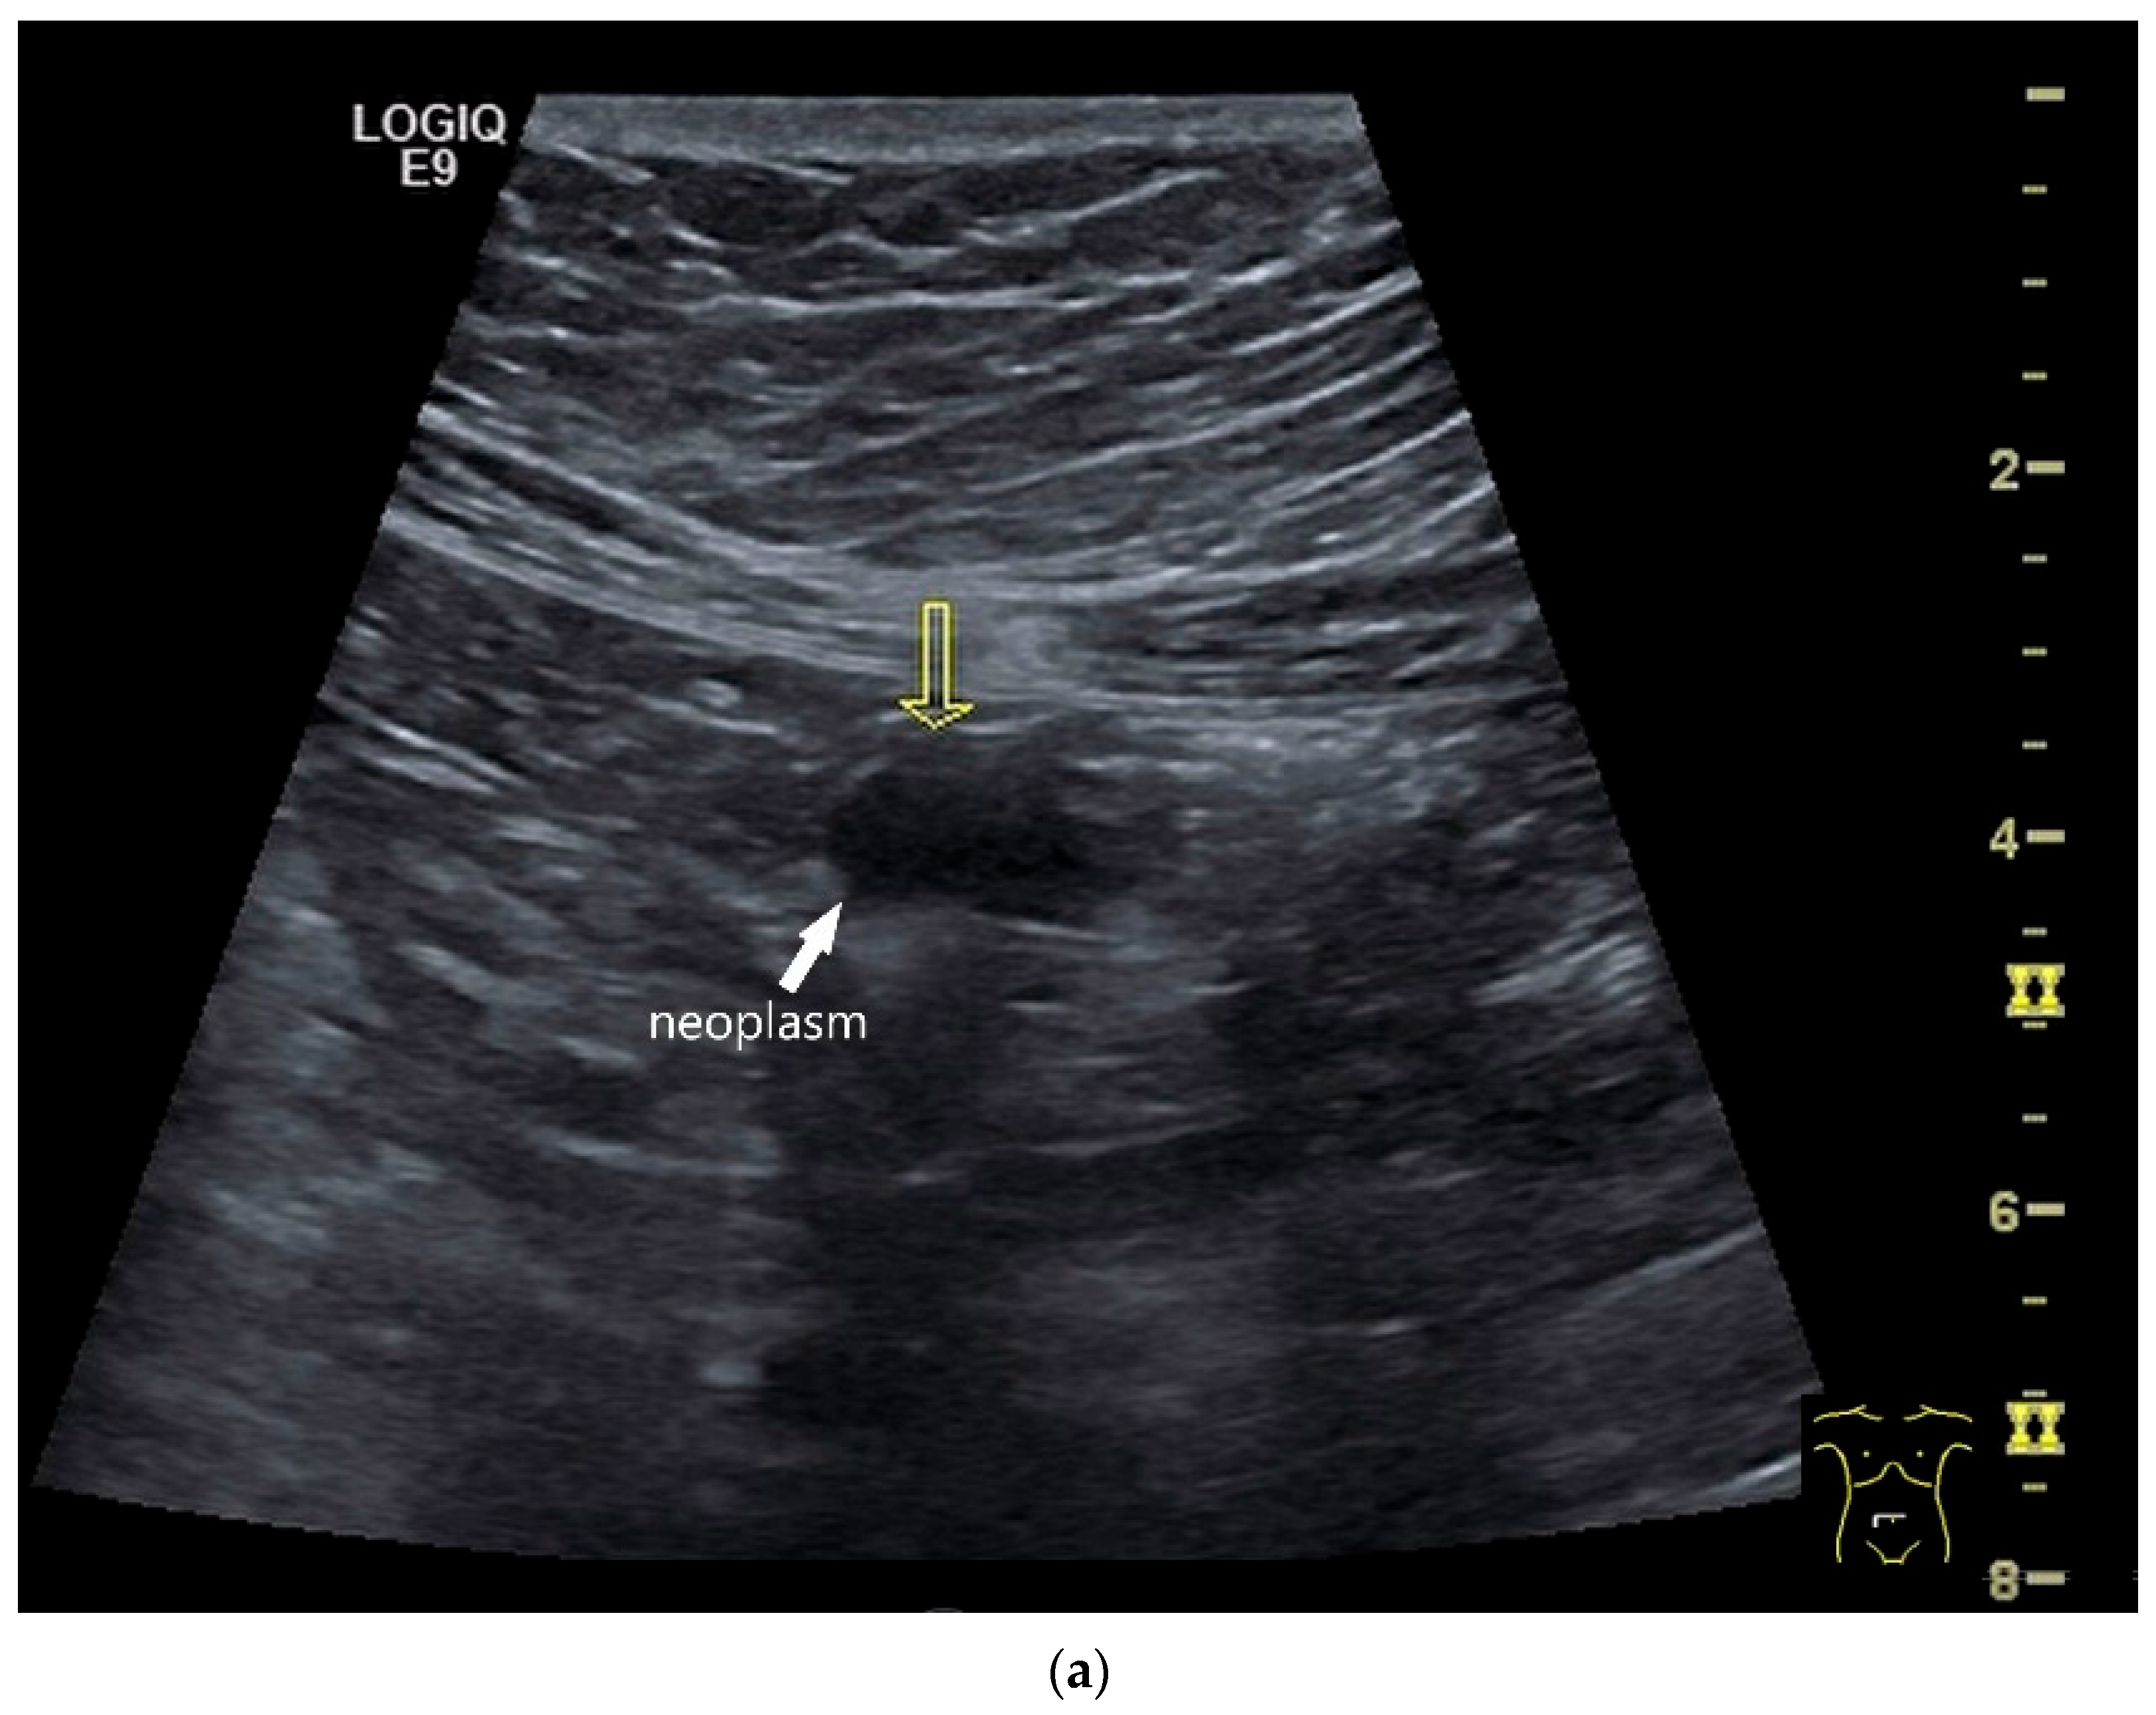

Figure 4.

NEN in the ileum: an approximately 14 mm hypoechoic nodular tumor is visible (a). Subsequently, peristalsis reveals a hypoechoic wall thickening (W) and hyperechoic luminal reflex (L) (b) and, finally, causes the tumor to be obscured by the luminal contents and dorsal artifacts (c). The region of the tumor is marked with a yellow arrow in all three images.